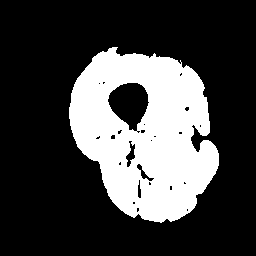

(c)

Finally, we define the set of corrected pseudo-labels as the intersection between the and masks. Examples are shown in Fig. 2.

Inspired by source-free domain adaptation approaches [8], we argue that the feature within the same category should lie closer to their class prototypes, enforcing a high correlation for samples of the same class. In the case of segmentation, image regions with highly correlated voxels in feature space often have compact intensity ranges [18]. Thus, instead of estimating the distance of a pixel to different class prototypes [13], we directly exploit the class prototype information hidden in the intensity distribution of a set of given regions. As the intensity values of the thigh muscle are mostly distributed in the range of after normalizing the input images () to the range , we extract coarse masks that exclude most of the IMF tissue. A single coarse mask is denoted as: